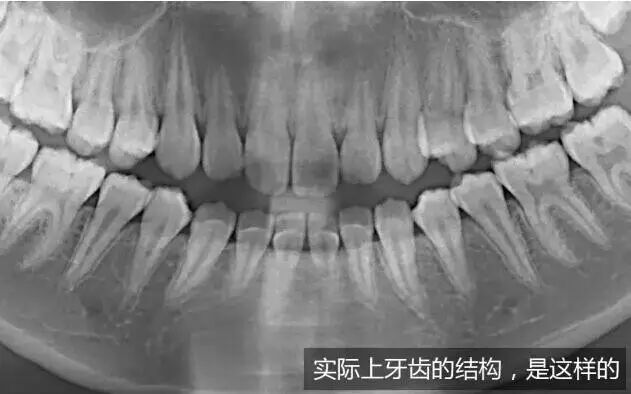

牙齿移动是一个生理性改建的过程,有点类似我们身体中的新陈代谢,是一个十分缓慢的过程。让我们来看看牙齿在矫正过程中,都在进行哪些变化:

我们可以看到,当牙齿进行移动后,牙根在骨中的长度并没有变短,所以,依旧像矫正前一样稳固。

因此我们得出一条结论:进行正规的牙齿矫正,利用的是牙齿自身可以在牙槽骨中移动这一特点,用轻柔的力量帮助牙齿移动,并且移动后的牙齿在牙槽骨中的长度没有改变,所以其稳固性也不会发生变化。